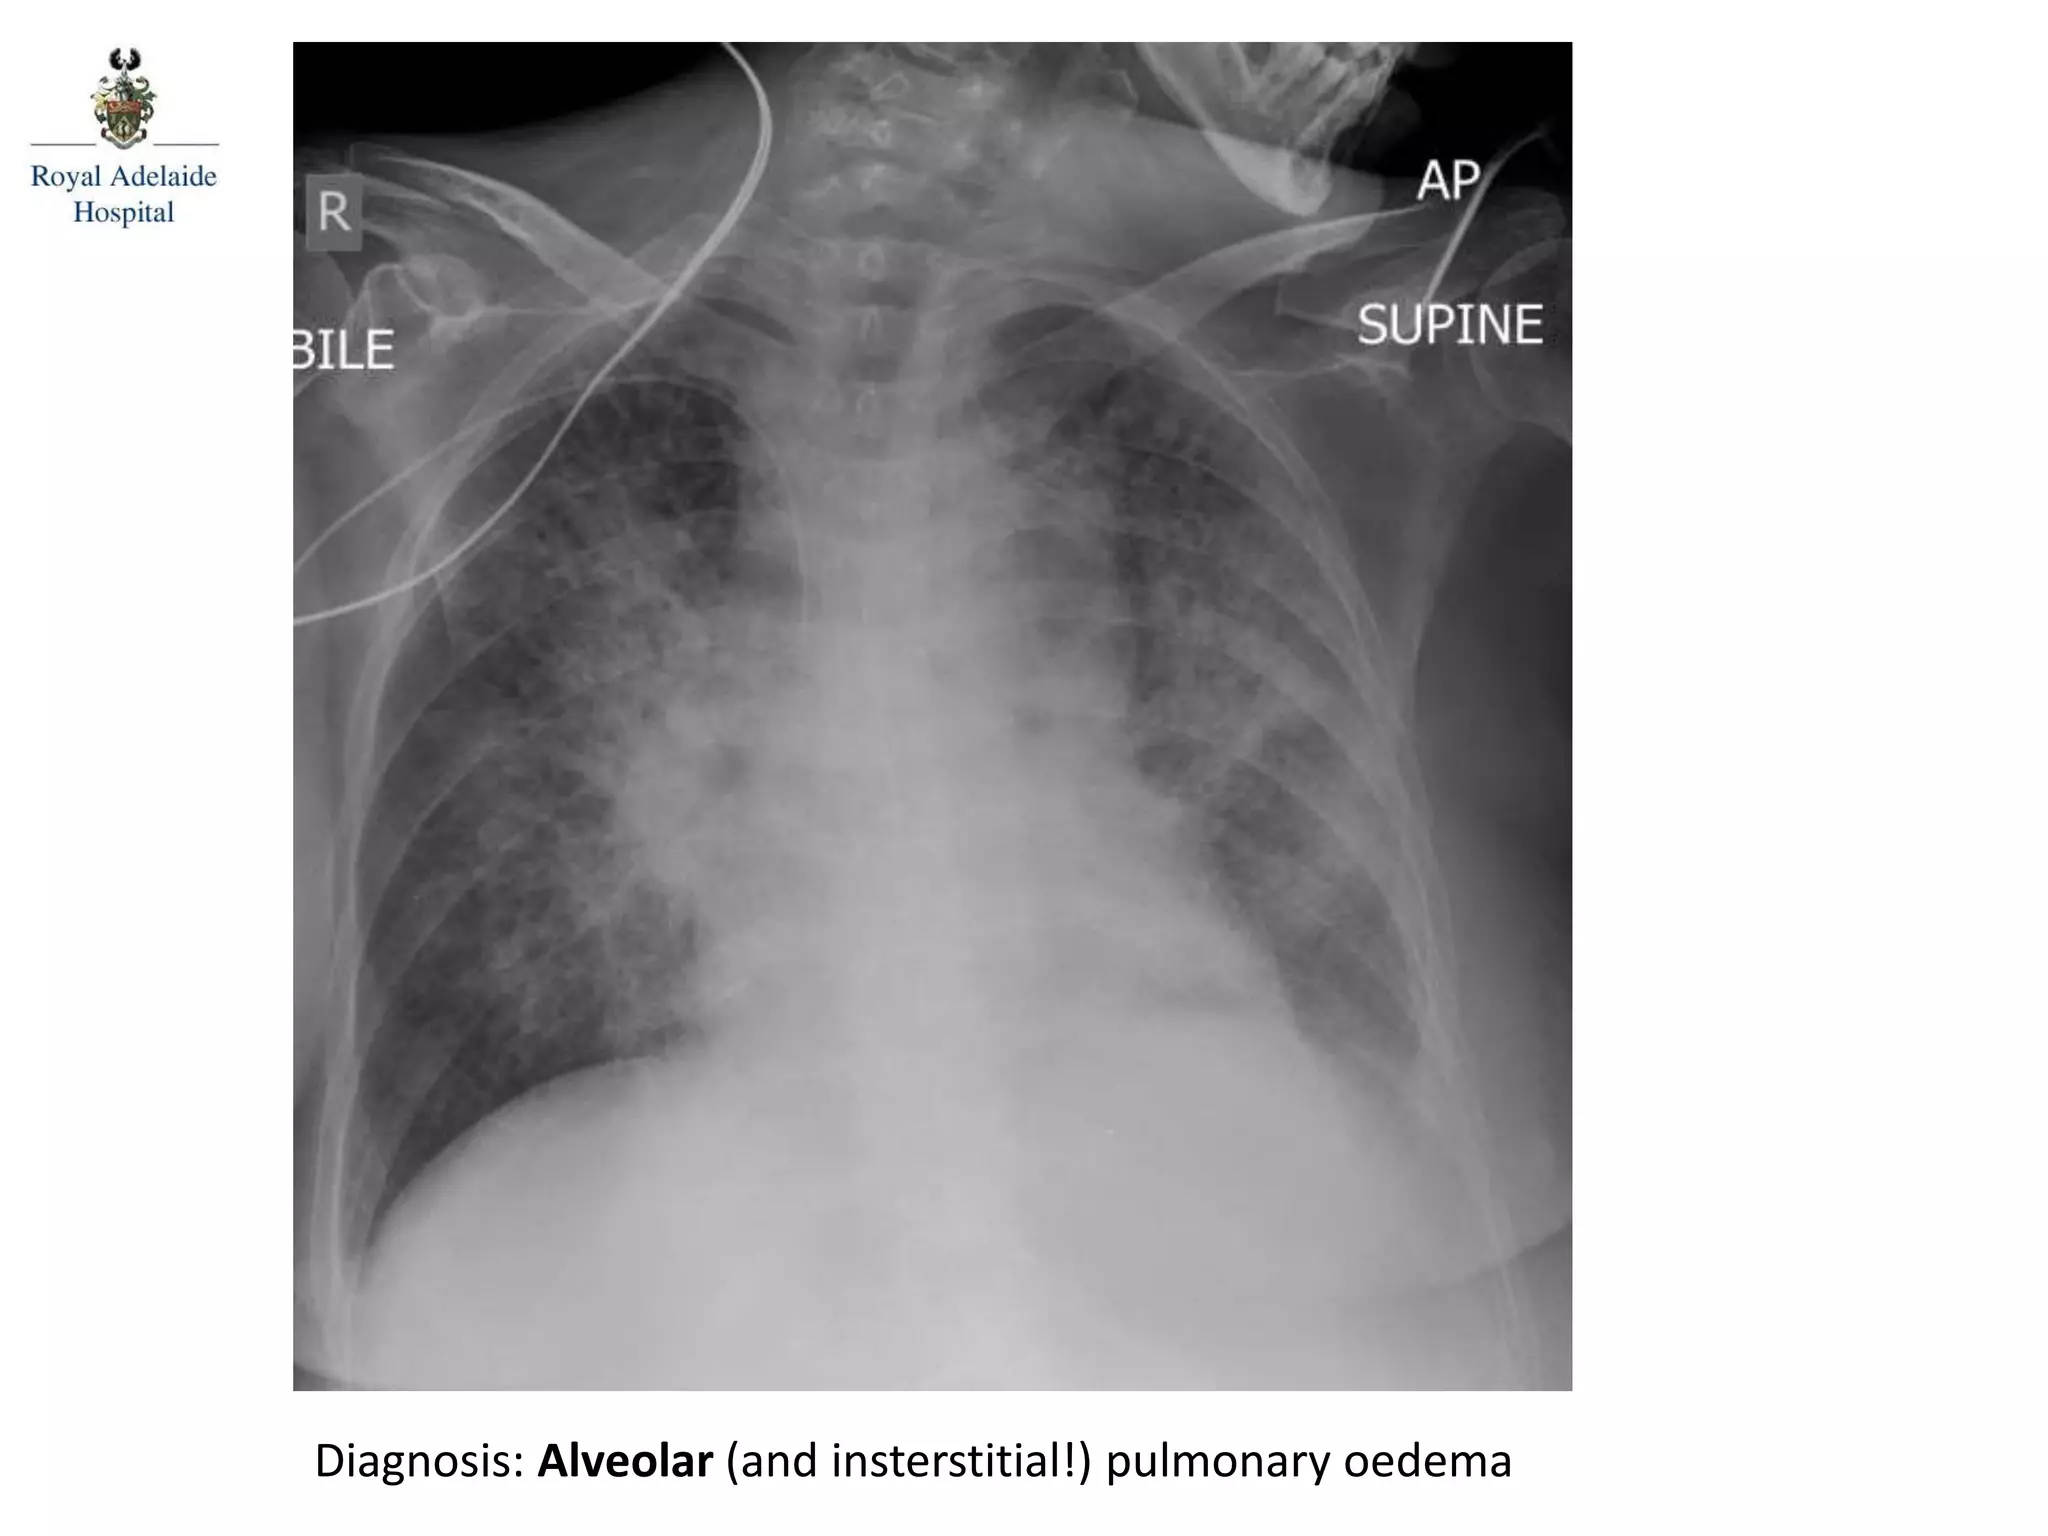

Diagnosis: Alveolar (and insterstitial!) pulmonary oedema